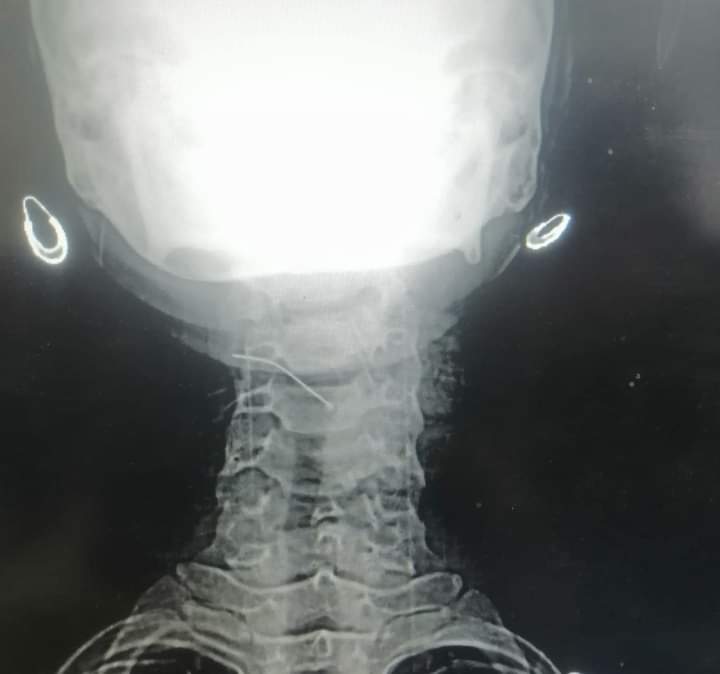

إنقاذ حياة طفلة ابتلعت "دبوس" بمستشفى الخارجة في الوادي الجديد

تمكن قسم جراحة الأنف والأذن والحنجرة بكلية الطب جامعة الوادي الجديد، من إنقاذ حياة طفلة تبلغ من العمر خمسة عشرة عامًا قامت بابتلاع دبوس حيث حضرت إلى طوارئ مستشفى الخارجة وتمكن الفريق باستخدام المنظار من استخراج الدبوس.

تكون الفريق من الدكتور حازم جمال نورالدين بقسم الأنف والأذن والحنجره والدكتور أشرف أخصائي التخدير بالمستشفى والدكتور محمود محمد علي مدرس مساعد بقسم الأشعه التشخيصية.